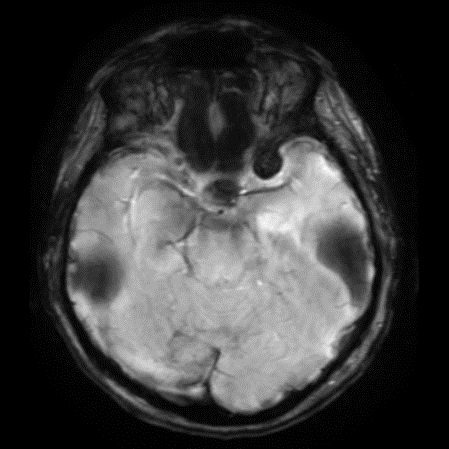

60 yaş, K

Baş ağrısı

Tanınız nedir?